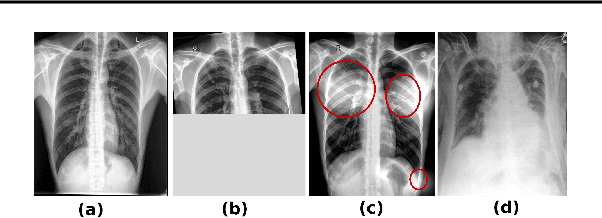

Pulmonary opacification is the inflammation in the lungs caused by many respiratory ailments, including the novel corona virus disease 2019 (COVID-19). Chest X-rays (CXRs) with such opacifications render regions of lungs imperceptible, making it difficult to perform automated image analysis on them. In this work, we focus on segmenting lungs from such abnormal CXRs as part of a pipeline aimed at automated risk scoring of COVID-19 from CXRs. We treat the high opacity regions as missing data and present a modified CNN-based image segmentation network that utilizes a deep generative model for data imputation. We train this model on normal CXRs with extensive data augmentation and demonstrate the usefulness of this model to extend to cases with extreme abnormalities.